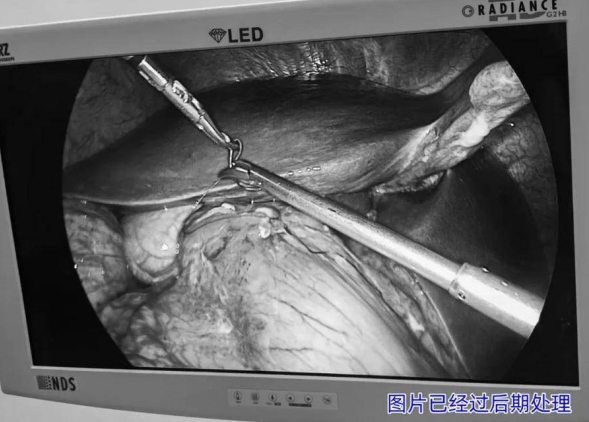

普外科团队迅速响应,根据患者情况制定了详细的手术方案。在手术室与麻醉科的密切配合下,由王兆太主任亲自带领普外科手术团队,为患者顺利实施了腹腔镜下胃溃疡穿孔修补术。手术过程顺利,患者术后恢复良好,目前已在进一步康复中。